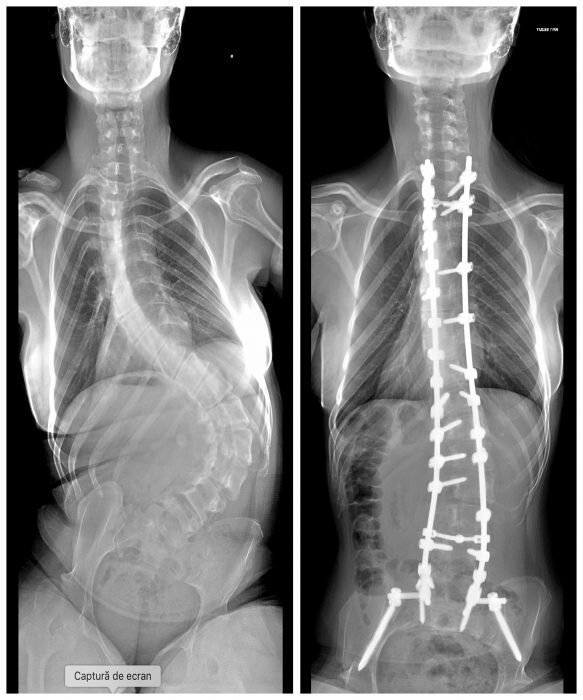

Băiatul în vârstă de 14 ani are nevoie de operaţie de corectare a scoliozei, o operație costisitoare care nu mai poate fi amânată, spun specialiștii. Degradarea foarte accentuată a poziţiei coloanei duce deja la presiuni pe organele interne printre care cel mai afectat este unul din plămâni, vena femurală va fi şi ea ştrangulată în timp limitând circulaţia sângelui prin aceasta. Displazia de şold tot mai accentuată poate duce la o luxaţie de şold, capătul femurului fiind deja foarte mult ieşit din cavitatea lui şi acest lucru va fi urmat de o complicaţie mai mare a stării lui Alex. De asemenea Alex nu mai poate sta nici pe scaun sau în fund pentru că are tendinţa să se răstoarne şi va fi determinat în timp să poată să şadă doar sprijinit pe mâna stângă, aceasta fiind mâna pe care el o poate folosi şi mâna cu care scrie.